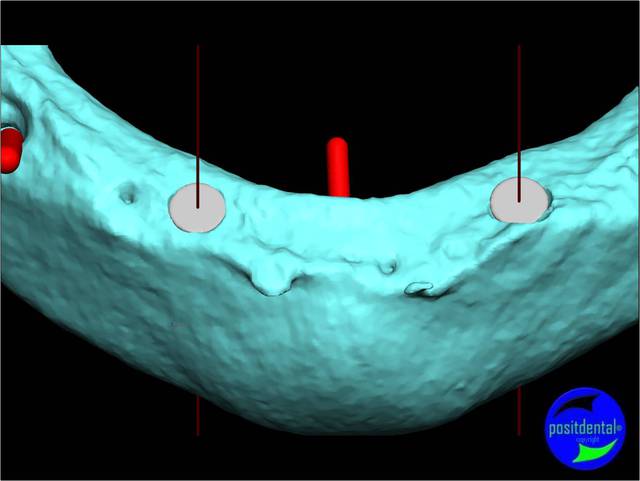

- la planification implantaire en 3D

Cas clinique n° 2

Guide chirurgical 005 sbqmwg - Eugenol

Guide chirurgical 003 capvkz - Eugenol

Guide chirurgical 004 f1p4ul - Eugenol